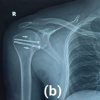

The patient was neurovascular intact. X-ray and CT scans were carried out, showing posterior shoulder dislocation with an osteocartilaginous lesion about 40% of the humeral head surface, localized on its anteromedial edge, representing a reverse Hill-Sachs lesion; type I according to Randelli’s classification (Fig. 1 & Fig. 2).